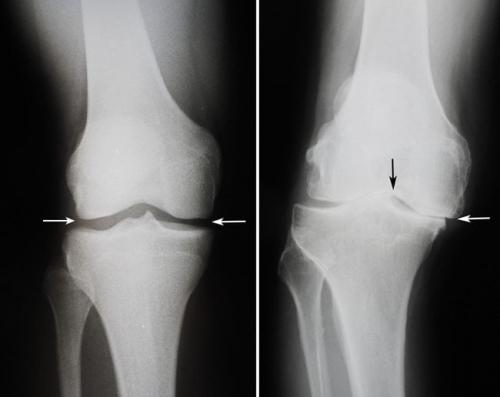

3. Комплексный сустав (art. complexa) , содержащий внутрисуставной хрящ, который разделяет сустав на две камеры (двухкамерный сустав). Деление на камеры происходит или полностью, если внутрисуставной хрящ имеет форму диска (например, в височно-нижнечелюстном суставе), или неполностью, если хрящ приобретает форму полулунного мениска (например, в коленном суставе).

Комплексные и простые суставы представлены в скелете человека коленным и межфаланговыми сочленениями.

- мыщелковый сустав — одна кость сочленения имеет округлый отросток, вторая в форме впадины, различны по размеру,